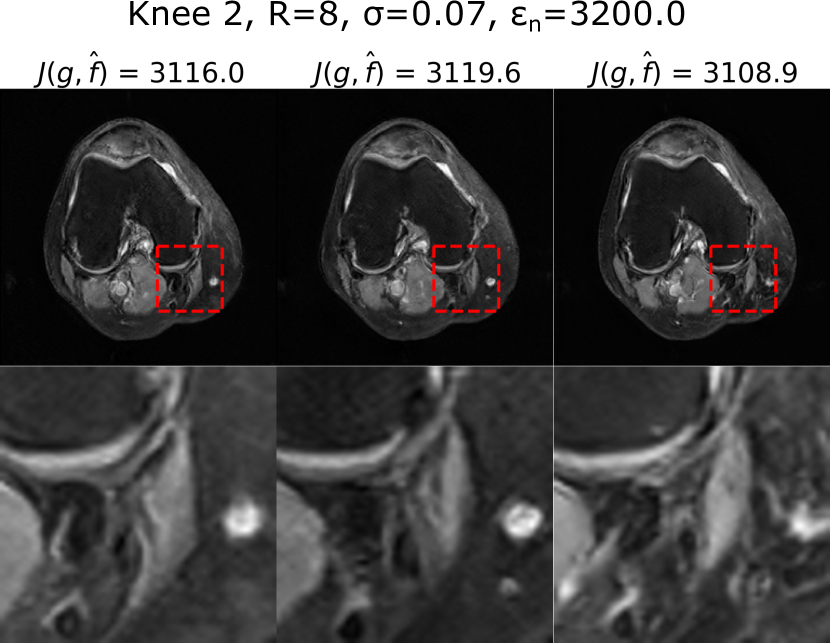

Figure 5 shows samples of data-consistent alternate solutions obtained with PULSE++ from k-space produced by Knee 1 when the sampling pattern or the noise level is varied, e.g. with sampling conditions {R=6𝑅6R=6, σ=0.07𝜎0.07\sigma=0.07} and {R=8𝑅8R=8, σ=0.05𝜎0.05\sigma=0.05}. The corresponding PULSE++ parameters were {γ=104𝛾superscript104\gamma=10^{-4}, λc=0.01subscript𝜆𝑐0.01\lambda_{c}=0.01} and {γ=105𝛾superscript105\gamma=10^{-5}, λc=0.001subscript𝜆𝑐0.001\lambda_{c}=0.001} respectively. Additionally, using the same pre-trained StyleGAN model, data-consistent alternate solutions were obtained with PULSE++ {γ=0.01𝛾0.01\gamma=0.01, λc=0.001subscript𝜆𝑐0.001\lambda_{c}=0.001} from k-space data with R=8𝑅8R=8 and σ=0.07𝜎0.07\sigma=0.07 corresponding to Knee 2 (Fig. 2), as shown in Fig. 6.

Refer to caption

Figure 6: PULSE++ can produce alternate data-consistent solutions for k-space data from different objects within the same distribution on which the StyleGAN is trained, as shown here for Knee 2 using the MRI-StyleGAN model with R=8𝑅8R=8 and σ=0.07𝜎0.07\sigma=0.07. Both the objects Knee 1 and Knee 2 belong to the NYU fastMRI dataset, but were excluded from the training set of the MRI-StyleGAN. Zoomed-in images of the same region in the alternate solutions indicated by a red bounding box show distinct structures. The alternate solutions are displayed in the grayscale range [0,1]01[0,1].